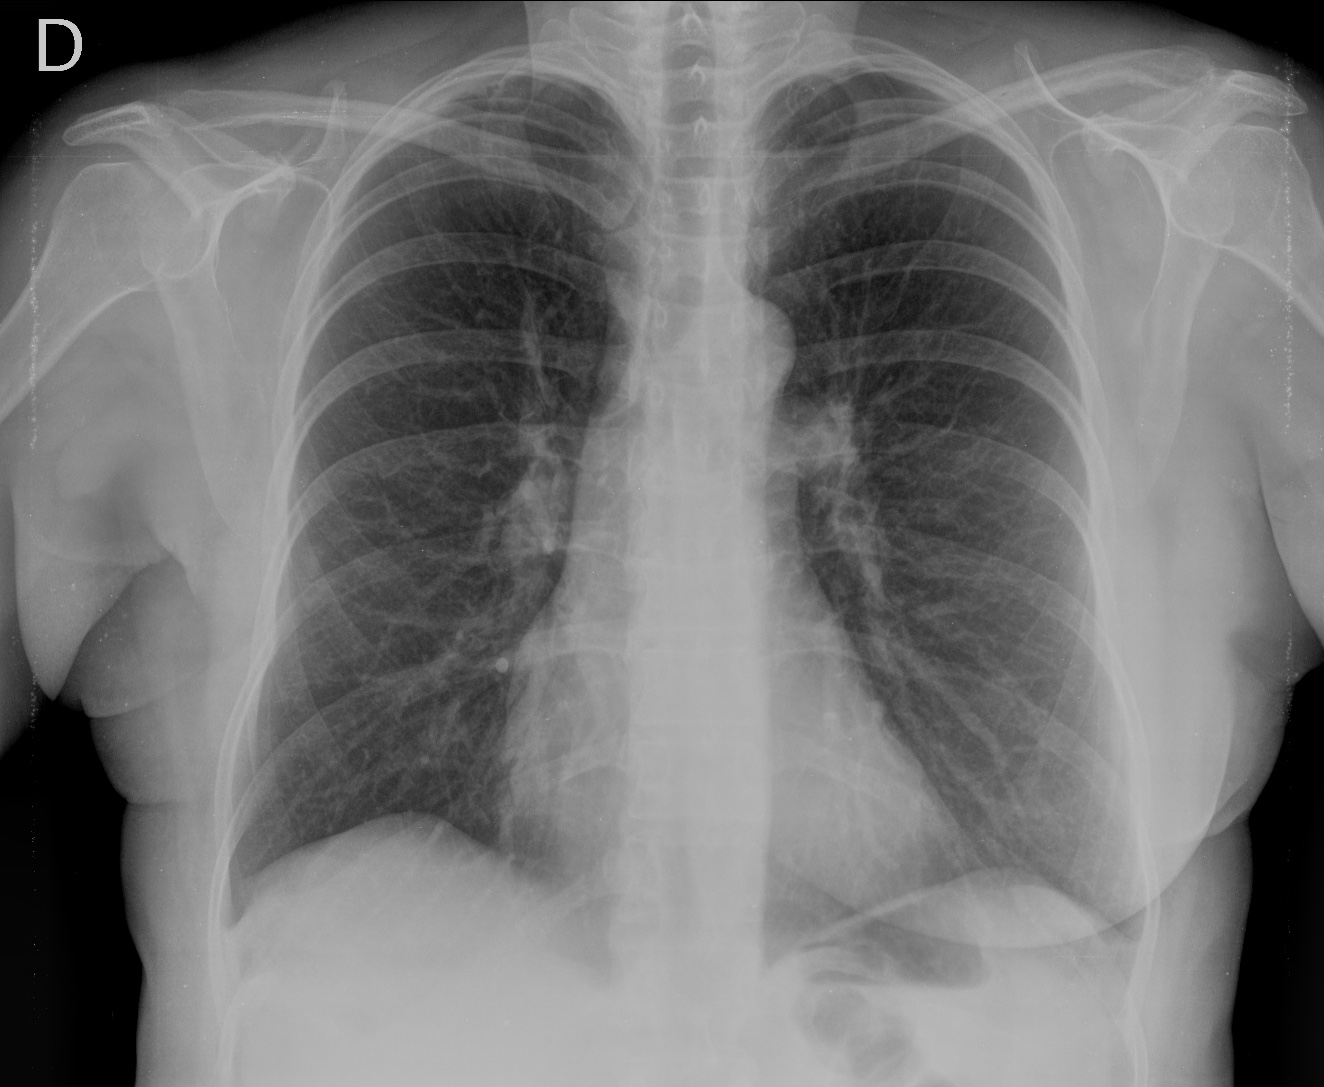

- En un principio podríamos decir que existe un aumento de densidad retrocardiaco que podría ser compatible con condensación neumónica a dicho nivel, sin embargo estamos ante una placa poco inspirada, lo cual puede llevarnos a cometer errores diagnósticos.

- Se recomendó volver a realizar la radiografía, observar a continuación:

Ya no se observa el aumento de densidad retrocardiaco, la placa es normal.

INSPIRACIÓN: Una placa bien inspirada es aquella en la que se observar 6-7 arcos costales anteriores o 10-11 arcos costales posteriores. Lo contrario puede producir imágenes falsas de condensaciones o de seudocardiomegalia.